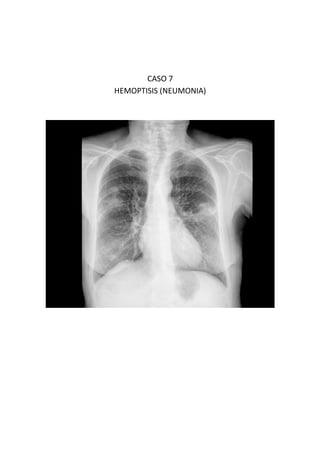

Este documento presenta 7 casos de patología torácica que serán discutidos en una sesión de interpretación radiológica. El objetivo es que los asistentes tomen notas aclaratorias durante la discusión interactiva de cada caso, en lugar de una mera explicación teórica. Los casos incluyen agenesia pulmonar derecha, situs inversus, estridor, neumonía con hemoptisis y enfermedad intersticial. El último caso involucra a un paciente de 86 años con tos y disnea que podría tener una consolidación en la base